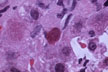

Councilmann body

Fig 26 - APOPTOSIS: This form of cell death appeares to be the normal way cells are renewed in every tissue.The cells condense,become round or spherical,separate from other cells,fragment and are phagocytized by histiocytes.This is the way lumina develop in tubular structures, limbs are fashioned, organs re reabsorbed in the metamorphosis of larvae and tailes are lost by tadpoles.The cells become dehydrated, and retain their organelles.There is no inflammatory reaction.In the liver the apoptotic cells are called Councilmann bodies.(1) (2).